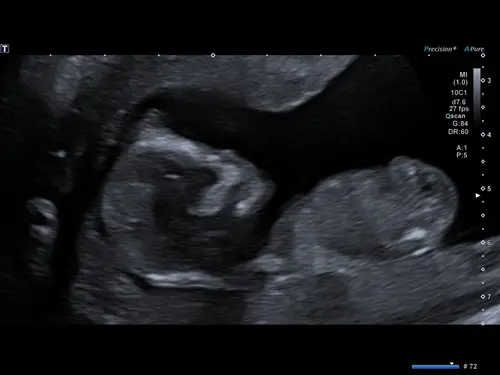

Wat denken jullie aan de hand van bovenste foto 🥹

Ik denk meisje